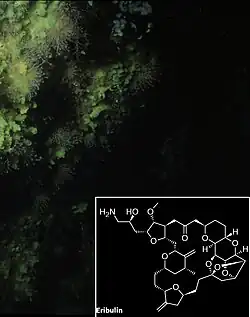

Размножаются половым и бесполым путями (в том числе с образованием покоящихся почек — геммул). Обладают высокой способностью к регенерации. Многие губки, а также населяющие их микроорганизмы вырабатывают биологически активные вещества, используемые в медицине.

| Обыкновенные губки | Морские, пресные (около 80—90 % всех известных видов губок)[144] | От приливной зоны до абиссали;[86] хищные обыкновенные губки могут быть найдены на глубине 8840 м[81] | Любые |

Губковые рифы и сообщества

Особым видом рифов являются губковые рифы[145]. Подобные рифы ранее были широко распространены в истории Земли[146]. Наиболее ранние из них датируются среднем триасом (245—208 млн лет назад), а своего наибольшего процветания они достигли в конце юрского периода (208—146 млн лет назад). В это время система губковых рифов, образованная преимущественно шестилучевыми губками и имеющая длину около 7 тысяч км, пересекала поперёк северный бассейн древнего океана Тетис; она является наиболее крупной среди известных конструкций, созданных когда-либо живыми организмами. Резкое сокращение количества губковых рифов произошло в меловом периоде на фоне всё возрастающего доминирования коралловых рифов[147].

Мелководные губковые рифы ныне отсутствуют, и все известные подобные рифы являются глубоководными[148]. Современные губковые рифы нуждаются в уникальных условиях существования, которые могут объяснить их редкость. Они возникают в желобах континентального шельфа, в местах с оптимальными для их развития условиями: со сравнительно низкой скоростью осадконакопления, с высокими скоростями течения[146], высокой концентрацией в воде диоксида кремния и низкой концентрацией кислорода, со стабильным морским дном, состоящим из камней, крупного гравия и крупных валунов, при температурном режиме воды 5,5-7,3 °C[147]. Губковые рифы в настоящее время известны на западе Канадского континентального шельфа[149], широко распространены в Северной Атлантике, в канадской Арктике и на континентальном шельфе в Антарктике[148]. Сформированный кремниевыми губками (Demospongiae) риф существует в Северном Ледовитом океане у острова Аксель-Хейберг[150]. Четыре рифа, образованные шестилучевыми губками в заливе Королевы Шарлотты на расстоянии 70-80 км от береговой линии и на глубине 165—240 м, занимают площадь 700 км² морского дна[148]. Некоторые губки из рода Heterochone в северной части Тихого океана могут создавать рифы высотой более 20 м, простирающиеся на несколько километров. Также вдоль глубоководных коралловых рифов обычно тянется зона обломков кораллов, в которой доминируют губки, среди которых имеются виды, разрушающие мёртвые кораллы[151]. В юго-западной части Баренцева моря имеются глубоководные сообщества губок и плеченогих[146].

Взаимоотношения с другими организмами

Симбиотические ассоциации

Губки могут вступать в симбиотические отношения с представителями большинства групп организмов[152]: с водорослями[153], грибами[154], прокариотами[155] и др.

Представители типа Porifera предоставляют среду обитания для многих одноклеточных и многоклеточных организмов. Многоклеточные организмы обычно выступают комменсалами и поселяются на поверхности тела губки и в её внутренних полостях, не мешая её жизнедеятельности[156]. Среди эндобионтов губок отмечены стрекающие, турбеллярии, немертины, сипункулиды, полихеты, моллюски, ракообразные, многоколенчатые, иглокожие, асцидии и рыбы[157].

Одноклеточными симбионтами губок могут быть динофлагелляты, зоохлореллы, красные водоросли, нитчатые зелёные водоросли, а также грибы[156]. Пресноводные губки наиболее часто находятся в симбиотических отношениях с различными водорослями, которые обусловливают их зелёную окраску[26].

Губки, в которых поселяются фотосинтезирующие эндосимбионты, выделяют в три раза больше кислорода, чем поглощают, а также продуцируют больше органического вещества, чем потребляют. Такая роль губок в образовании первичной продукции особенно важна в австралийском Большом Барьерном рифе, но в Карибском море она не столь велика[158].

Однако особенно важными симбионтами губок являются облигатные видоспецифичные автотрофные или неавтотрофные прокариоты (бактерии и археи), которые поселяются в мезохиле. Взаимодействие между губками и этими микроорганизмами может происходить по-разному. Уникальность симбиоза губок с прокариотами заключается в том, что все исследованные к настоящему времени виды губок имеют симбиотические ассоциации с одним или более видами бактериальных симбионтов[155][159][160][161].

Прокариотические симбионты, как правило, располагаются между элементами мезохила и физически отделены от воды пинакодермой. Однако известны губки, у которых симбионты внутриклеточные: они локализованы в специальных клетках — бактериоцитах[162]. Биомасса прокариотических эндосимбионтов может быть весьма значительной и составлять до 40 % (и даже до 60 %) массы губки-хозяина, а концентрация бактериальных симбионтов в губке может на 2-3 порядка превышать концентрацию прокариотических организмов в окружающей водной среде[163]. Прокариоты могут проникать в тело губки двумя путями: из воды в окружающей среде, или же путём вертикального переноса от материнской губки к следующему поколению через яйца или личинки; возможность вертикального переноса прокариотических симбионтов говорит об их исключительной важности для жизни губок. Губкам удаётся поддерживать разнообразные, но в то же время специфичные микробные сообщества внутри себя — несмотря на то, что вместе с током воды при фильтрационном питании в их тела проникает множество морских микроорганизмов[164].

Внутри губок поселяются прокариоты самого разнообразного систематического положения, относящиеся примерно к 20 бактериальным филам, причём представители одной филы — Poribacteria — встречаются исключительно в губках. Симбиотические прокариоты могут принимать участие в разнообразных физиологических процессах губок — например, в круговороте нерастворимых белков и структурных перестройках органического скелета и внеклеточного матрикса. Многие прокариоты-симбиоты синтезируют антибиотики и вещества с резким запахом, отпугивающим хищников. Они также могут служить дополнительным источником питания губок, причём могут поглощаться как сами прокариоты путём фагоцитоза, так и продукты их жизнедеятельности[165]. Можно сказать, что губка-хозяин и населяющие её микроорганизмы метаболически связаны и обмениваются соединениями азота, продуктами фиксации СО2, вторичными метаболитами и полученными из воды органическими соединениями[164]. Например, внутри губки Lophophysema eversa живут автотрофные микроорганизмы, способные окислять аммоний, нитрит и сульфид и потому играющие важную роль в круговороте углерода, азота и серы в теле губки. Кроме того, они нейтрализуют токсичные для губки-хозяина аммоний, нитрит и сульфид[166].

Губки вступают в разнообразные взаимоотношения с другими животными. Например, довольно крупная губка Lissodendoryx colombiensis, живущая на каменистых субстратах, может также заселять заросли морских трав. При этом она позволяет окружать и обрастать себя губкам, живущим в морских травах и опасным для местных морских звёзд; таким образом, Lissodendoryx colombiensis обеспечивает себе защиту, а губки зарослей морских трав получают возможность жить на некотором поднятии относительно морского дна[167].

Особенным разнообразием отличаются взаимоотношения между ракообразными и губками[26]. Многие виды мелких веслоногих и равноногих рачков, бокоплавов сожительствуют или паразитируют в губках. Часто десятиногие раки и креветки используют губок в качестве убежища от врагов. Креветки рода Synalpheus из семейства Alpheidae образуют колонии внутри губок, причём каждый вид креветок населяет только определённый вид губок; благодаря этому род Synalpheus является одним из самых многочисленных родов ракообразных. Вид Synalpheus regalis использует губок не только для питания, но также для защиты от других креветок и хищников. В одной губке может жить 16 тысяч особей креветок, питающихся самыми крупными частицами, попадающими внутрь тела губки при фильтрационном питании[168][169]. В другом семействе креветок — Spongicolidae — практически все представители являются облигатными симбионтами глубоководных стеклянных губок (только в роде Microprosthema известны свободноживущие формы)[170]. В частности, самец и самка из рода Spongicola поселяются в полости стеклянной губки Euplectella oweni на стадии личинки, а во взрослом состоянии выйти за остов губки уже не могут[26].